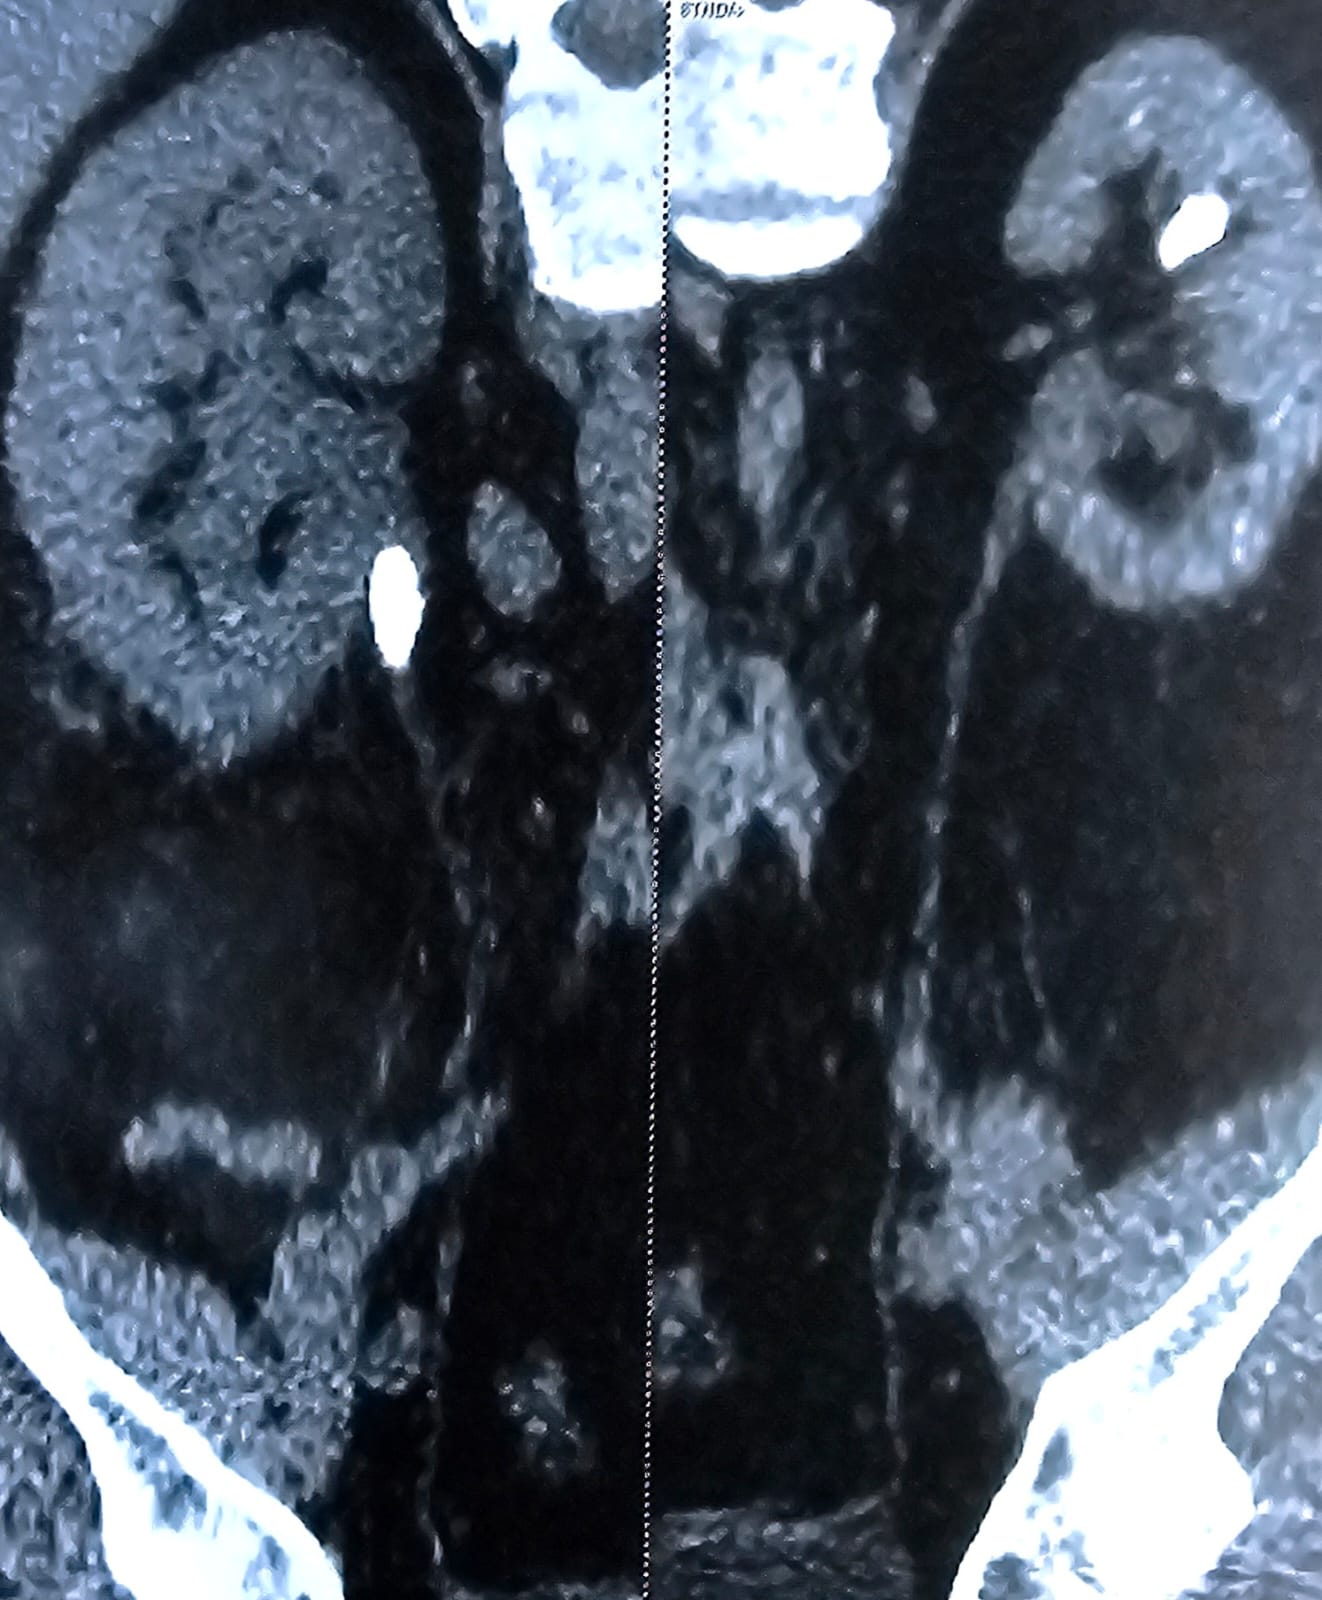

Actual surgical samples of our precision technology

NCCT